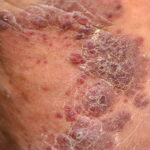

The typical patient with classic KS is a Caucasian male in his sixties with a Mediterranean or Jewish background. The tumors usually start on the skin of the distal portions of the lower extremities as unilateral or bilateral bluish-red (hematoma-like) macules. These lesions tend to progress slowly both horizontally and vertically and develop into firm plaques (Fig. 128-1) and, eventually, into nodules. During tumor progression the color changes to brownish and the skin overlying the tumor becomes hyperkeratotic and, in particular on the lower extremities, may ulcerate. Surrounding the tumor there is frequently a pitting edema which may evolve into fibrosis. Classic KS usually runs a rather benign course slowly extending proximally and patients may sometimes live with slowly progressive disease for decades.38,39,41 After several years of progression (Fig. 128-2), dissemination to other body sites is frequently seen, and tumors may become manifest in lymph nodes, on mucous membranes, and in internal organs such as the gastrointestinal tract where it is rarely symptomatic.41,38 Because classic KS affects mostly elderly patients, death from other causes may precede its full spread.

AIDS KS differs from classic KS by its more rapid course and its rapid multifocal dissemination: early AIDS-KS lesions appear as small oval violaceous macules that develop rapidly into plaques and small nodules. They are frequently present at multiple locations at

disease onset and have a tendency for rapid progression. In contrast to other variants of KS, the initial lesions in AIDS patients frequently develop on the face, especially on the nose, eyelids, and ears, and on the trunk, where the lesions follow the relaxed skin tension lines . If untreated, disseminated AIDS-KS lesions may coalesce to form large plaques involving large areas of the face, the trunk, or extremities and lead to functional impairments. The oral mucosa is frequently involved and represents the presenting site in 10 percent to 15 percent of AIDS KS . Involvement of the pharynx is not uncommon and may result in difficulty eating, speaking, and breathing.

The histopathology of KS is dependent on the stage of KS development. Early patch-like lesions exhibit rather discrete histopathologic changes, consisting mainly of an increase in the number of dermal vessels, outlined by slightly irregular endothelial cells (Fig. 128-5). These vessels, located mainly in the superficial dermis are parallel to the skin surface, are frequently slightly irregular, and may form bizarre slits and clefts. In the surrounding skin focal hemosiderin, deposits and extravasated erythrocytes can be found as well as a moderate inflammatory infiltrate. Important differential diagnoses of this stage include lymphangioma and granulation tissue.

The pathology of KS plaques is more characteristic and reveals extensive vascular proliferation at all levels of the dermis with multiple dilated and angulated vascular spaces dissecting the collagen leaving a spongy network of collagen tissue. A characteristic sign of KS papules is the presence of solid cords and fascicles of spindle cells arranged between the jagged vascular channels. This biphasic angiomatous and solid tumor morphology changes to a clear-cut sarcomatous morphology with progression of the disease.

Nodular lesions consist predominantly of spindle cells arranged in bundles and interlacing fascicles and interspersed, irregular, slit-like vascular spaces without endothelial linings. Advanced lesions may display pronounced pleomorphism, nuclear atypia, and mitotic figures. At the periphery of solid tumors, (lymph) angiomatous-like portions of KS with bizarre vascular lumina and intravascular and extravasated erythrocytes, as well as siderophages, may be preserved. Erythrocytes, which appear as eosinophilic globules, are trapped within the slits and clefts formed by the spindle cells and erythrophagocytosis are occasionally observed. As in all other stages of KS, a moderate inflammatory infiltrate consisting of lymphocytes, histiocytes, plasma cells, and, sporadically, neutrophils is regularly present.